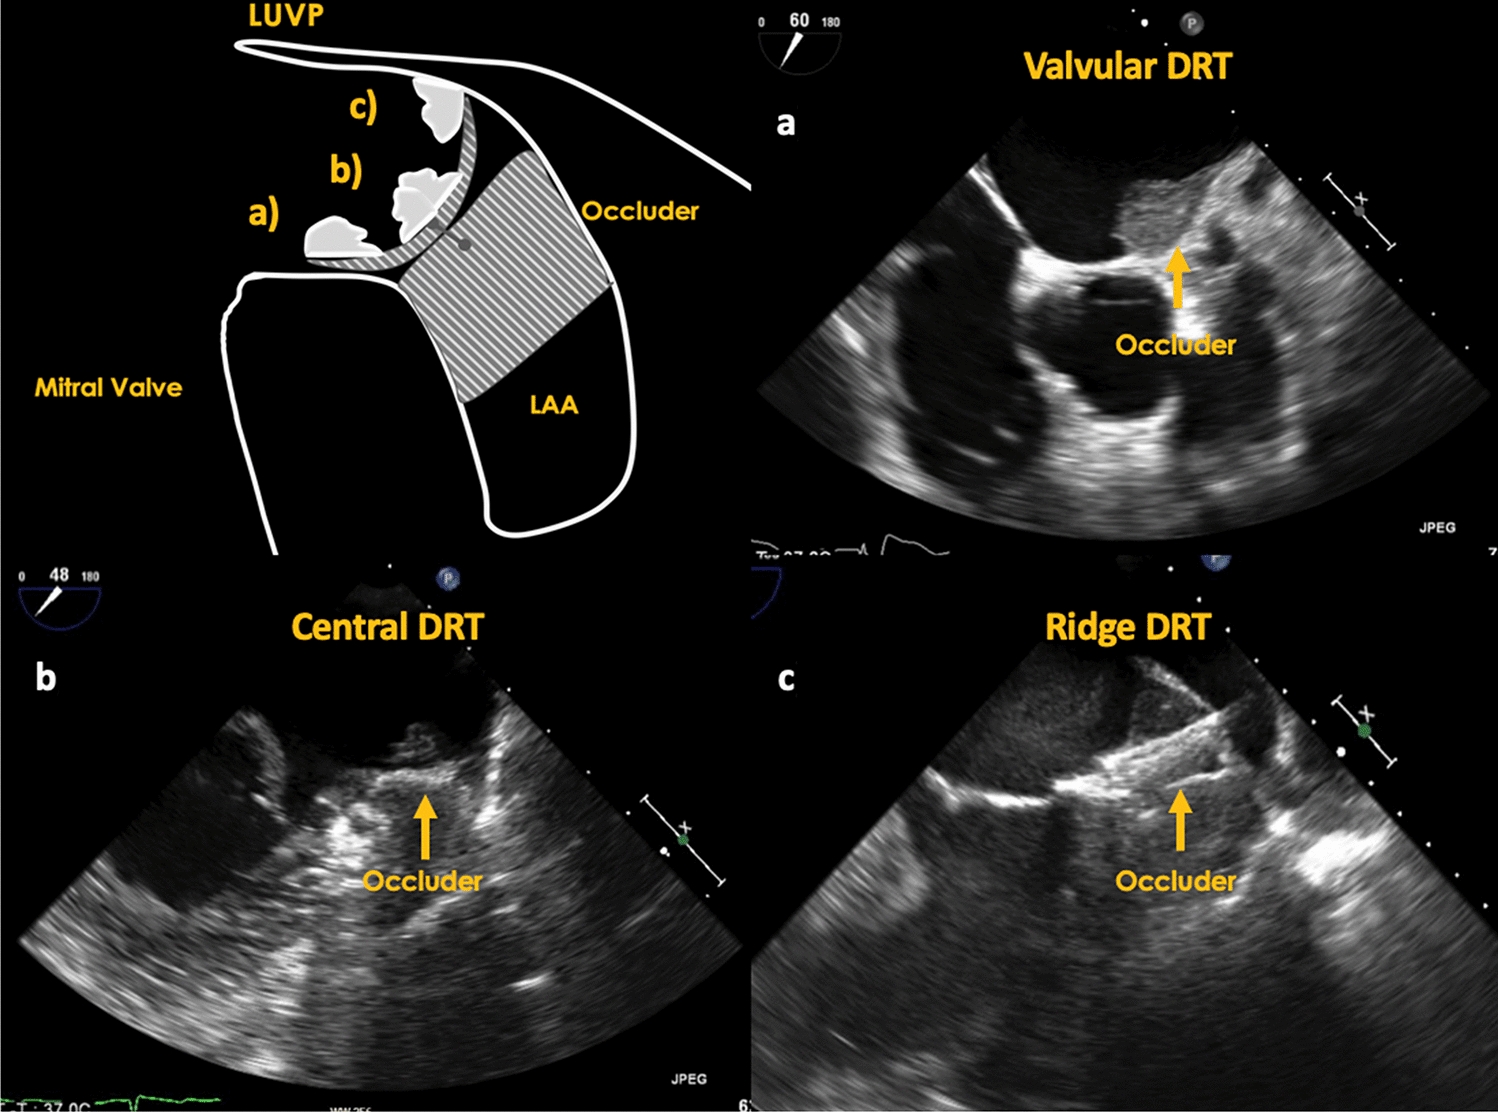

Occluder type and position

Fig. 3

Evidence of DRT in different LAA occluder types. a DRT on a Watchman occluder (non-pacifier occuder), b DRT on an Amplatzer Amulet (pacifier occluder)